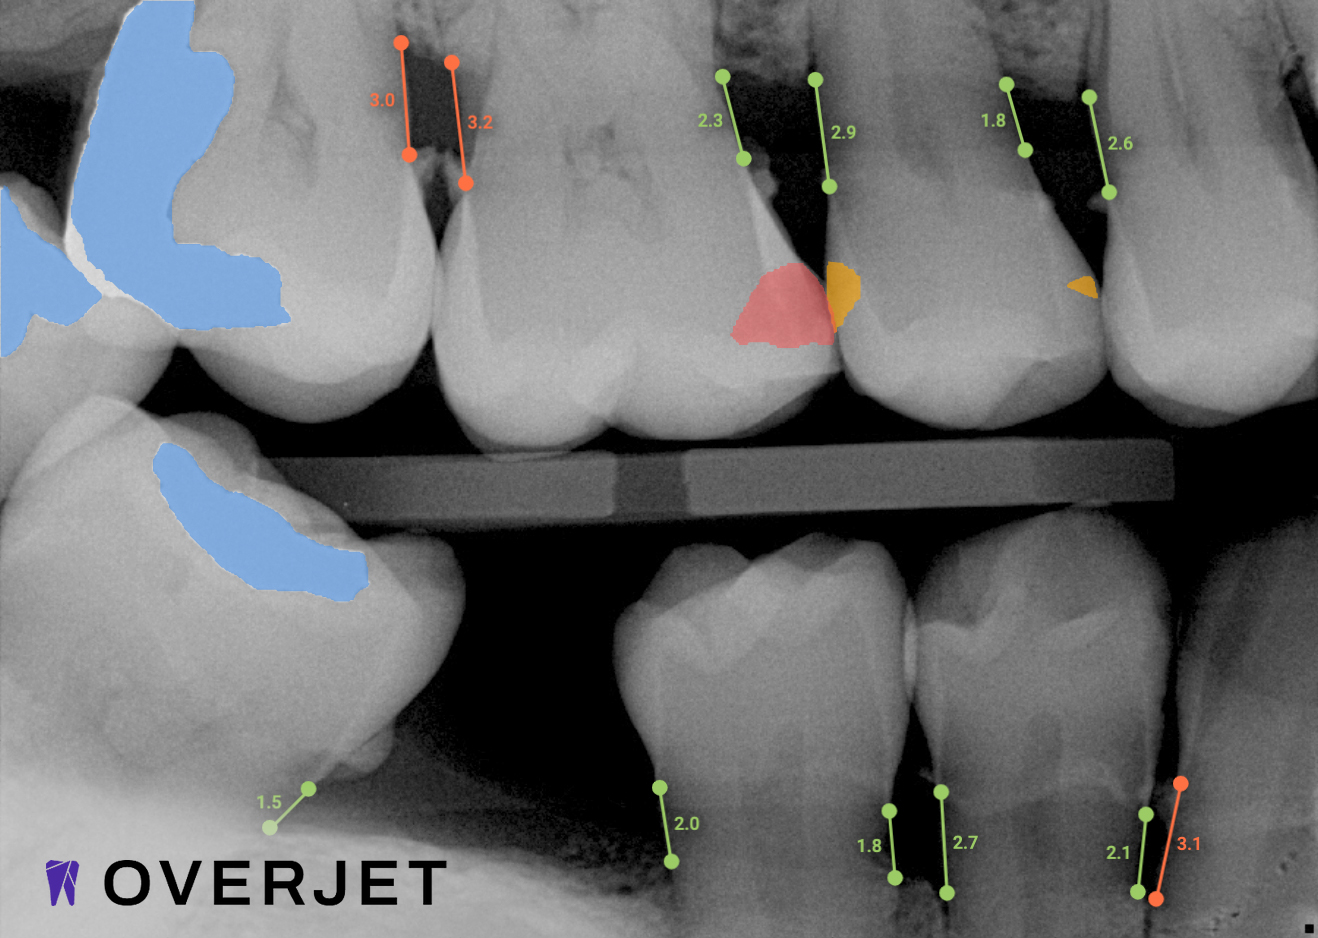

Overjet’s artificial intelligence technology transforms traditional black-and-white X-rays by adding a layer of data that instantly outlines decay (cavities) and measures bone loss. This makes it easy for you to see your results alongside your dentist. It’s like getting a second opinion delivered instantly. With Overjet’s analysis and easy-to-read presentation, you will have the information you need to make an informed decision about your oral health. Together, we’ll review your findings and discuss the best steps to take to achieve your goals.

Overjet’s artificial intelligence technology transforms traditional black-and-white X-rays by adding a layer of data that instantly outlines decay (cavities) and measures bone loss. This makes it easy for you to see your results alongside your dentist.